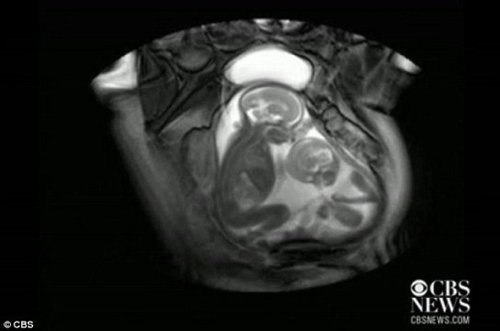

核磁共振成像技術(shù)顯示,一對雙胞胎在媽媽肚子里拳腳相向“掐架”

中新網(wǎng)12月1日電 據(jù)外媒報道,近日一段對孕期20周孕婦的核磁共振的掃描視頻顯示,一對雙胞胎還在媽媽肚子里就開始揮動手腳 “掐架”,令人感到神奇又搞笑。工業(yè)加濕機

據(jù)報道,英國倫敦帝國理工學(xué)院(Imperial College)胎兒保健中心本打算用核磁共振成像儀來診斷共享一個胎盤和同一個血液供應(yīng)系統(tǒng)的胎兒雙胞胎輸血癥候群(twin transfusion syndrome)情況,卻意外拍到了子宮中雙胞胎的“大戰(zhàn)”。機房專用加濕機

視頻顯示,畫面右邊個子稍小的胎兒在對左邊稍大的胎兒揮動手腳,“拳打腳踢”,似乎打算用身體爭得更多空間。而后者比較安分,也動了動嘴,縮了一下身子。